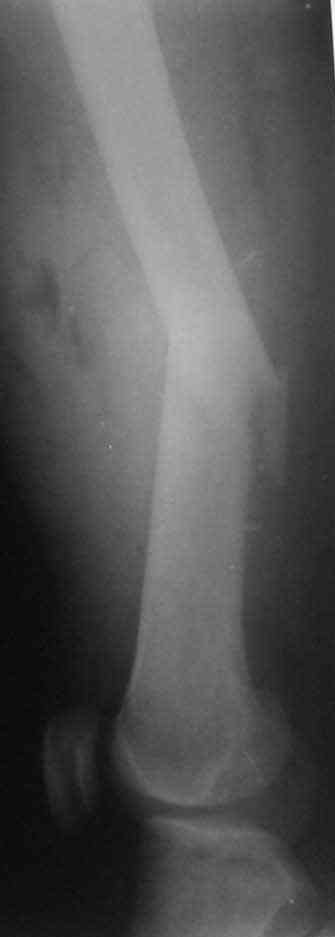

Несмотря на высокоэнергетический характер ранения, пуля не попала непосредственно в кость, а прошла рядом. Таким образом, для бедренной кости это ранение нельзя назватьв полном смысле этого слова высокоэнергетическим. К сожалению, не видно выходное отверстие. В любом случае, при таком переломе интрамедуллярный остеосинтез вполне показан. Кроме того, если пациент попал к Вам в первые часы после ранения, рана не должна рассматриваться как инфицированная. В качестве примера возможности даже более травматичной операции при таком характере перелома привожу следующий случай.

Пациент оперирован на 5-е сутки (переведен из другого лечебного учреждения)после сквозного пулевого ранения плеча и грудной клетки (непроникающее ранение той же пулей). Выполнен минимально инвазивный остеосинтез блокируемой метадиафизарной пластиной, повторная хирургическая обработка ран плеча. Заживление всех ран первичное, сращение наступило в обычные сроки.